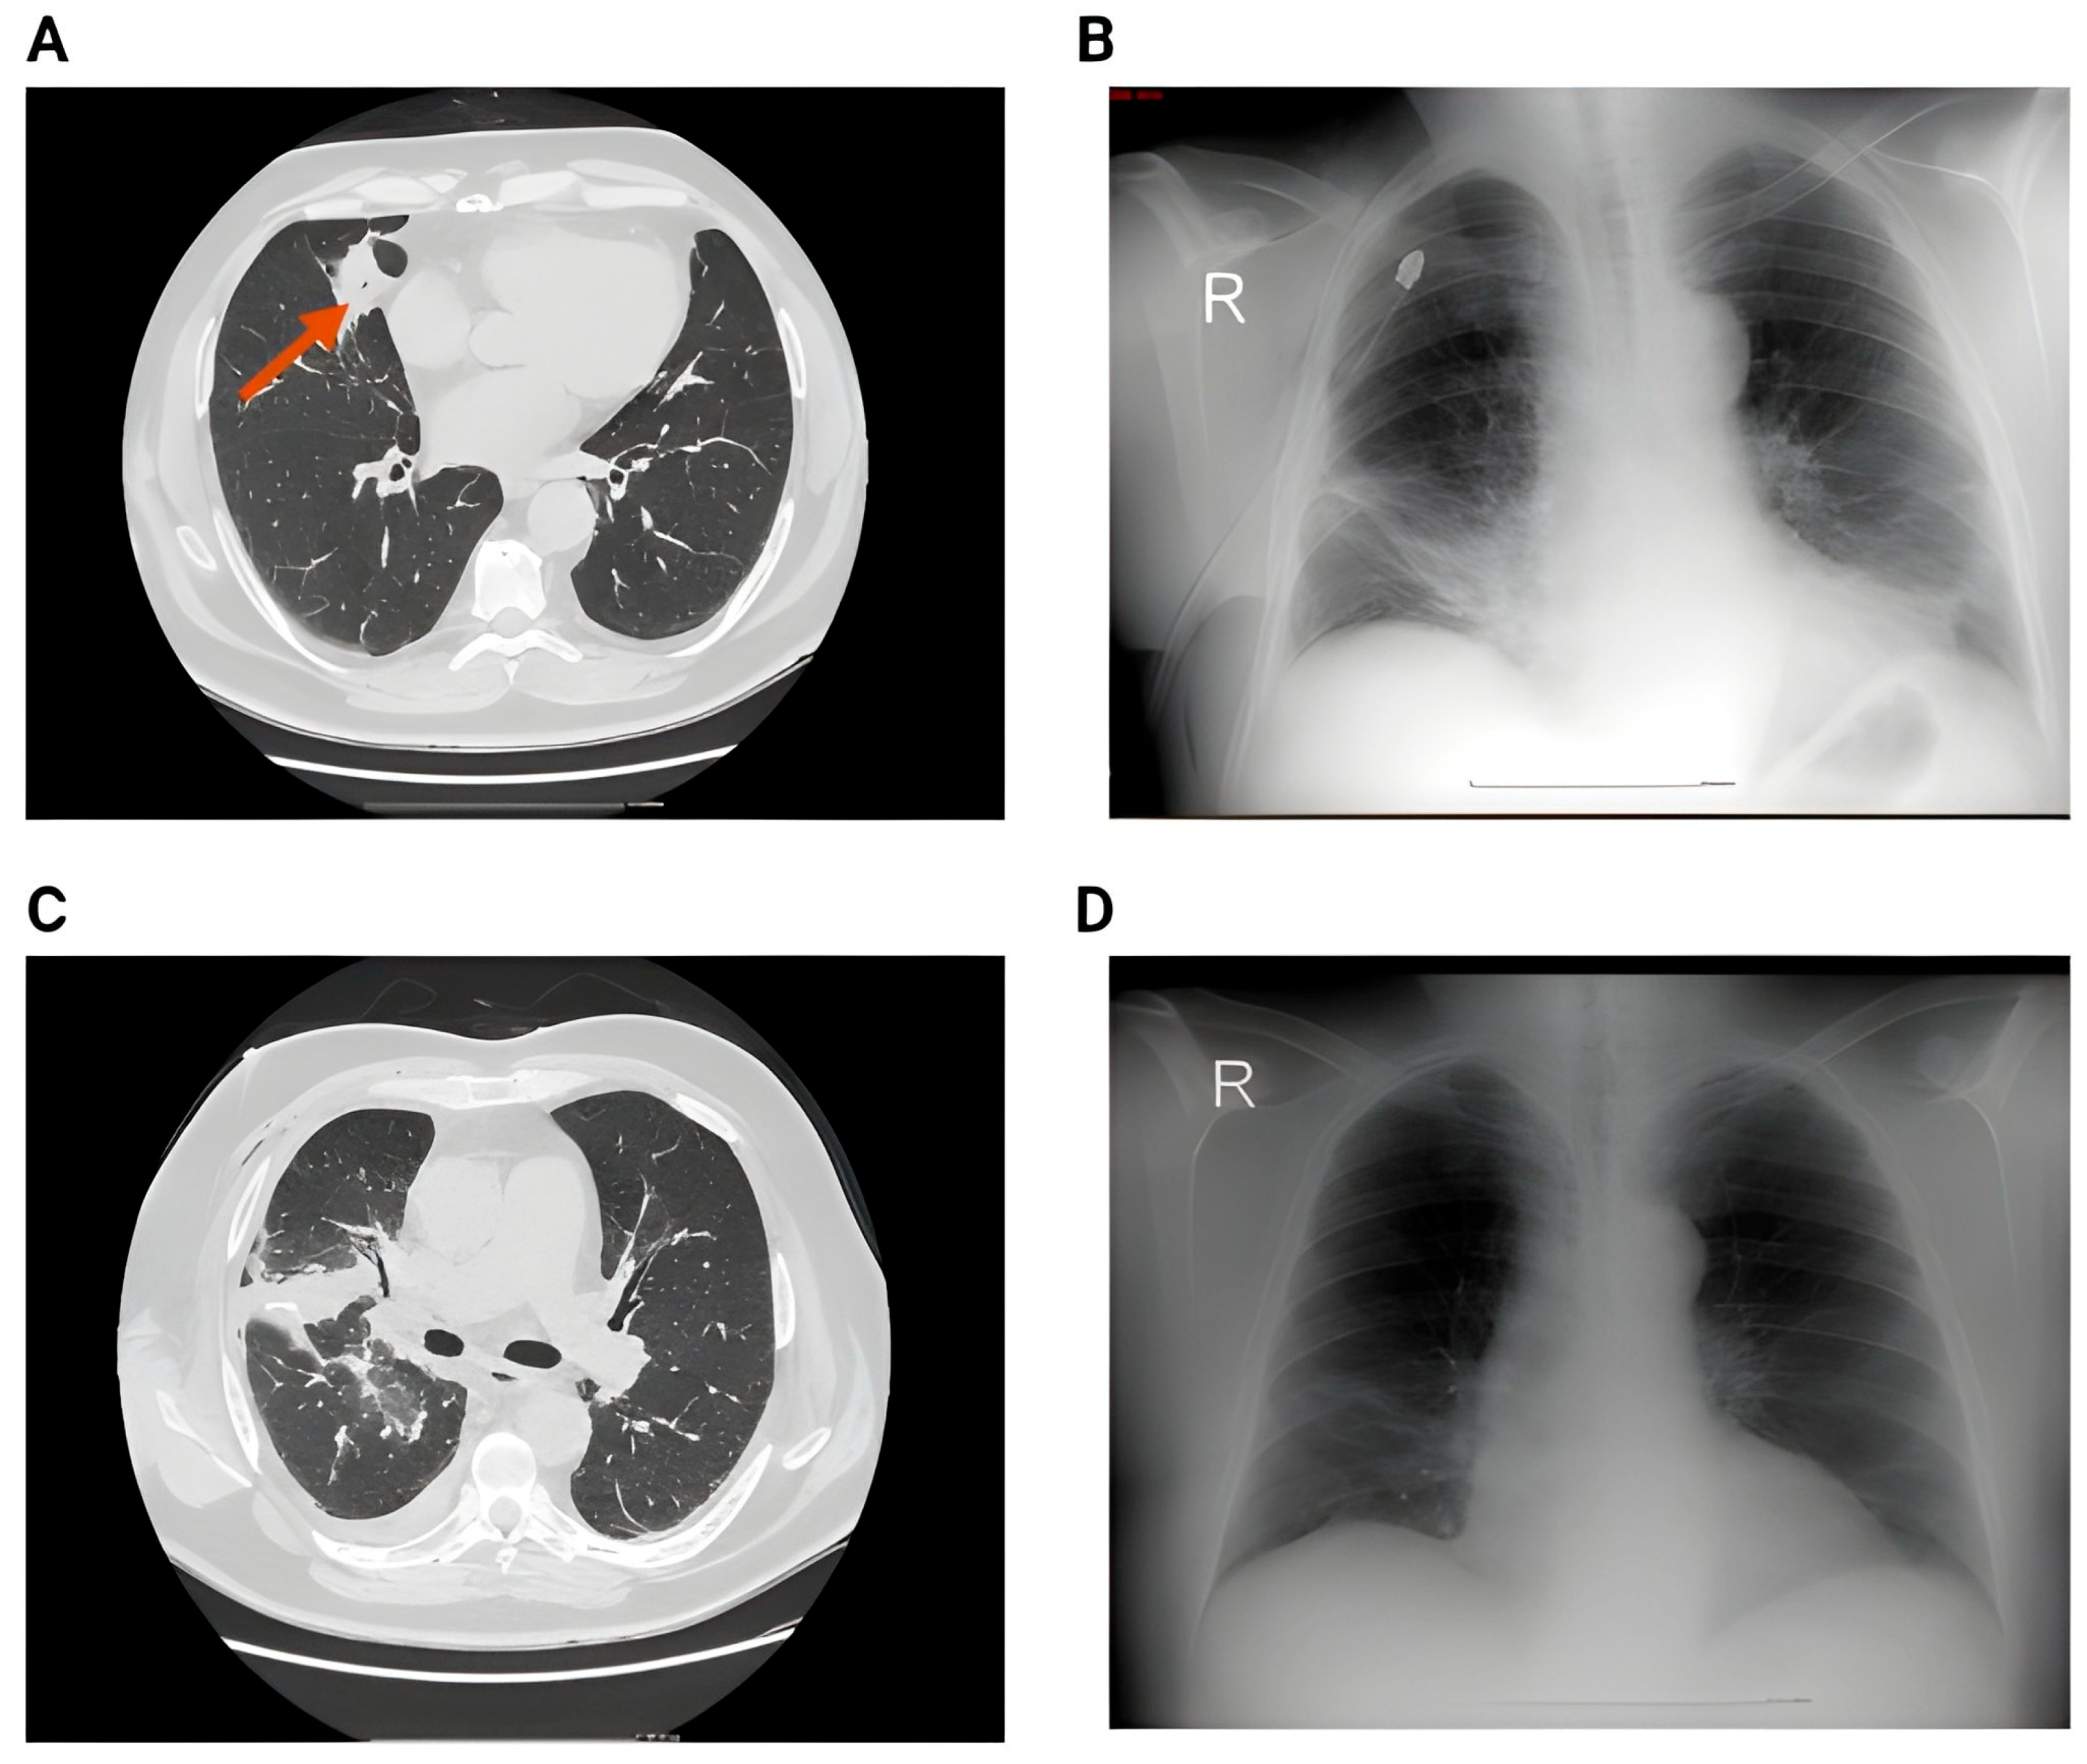

Figure 6 presents additional representative imaging findings that illustrate the postoperative spectrum following lobectomy.

CT scans revealed minor parenchymal alterations that chest radiography missed. More selectively utilized imaging methods included abdominal ultrasonography (57.6%), echocardiography (40.8%), PET-CT (16%), thoracic MRI (8.8%), and bronchoscopy (11.2%). Rarely did PET-CT and MRI reveal metastatic disease or pleural abnormalities in this sample.

Figure 6. (A) Preoperative CT showing singular nodule in the left upper lobe with peri-nodular fibrosis. (B) 2nd day postoperative showing left pneumothorax and small subcutaneous emphysema. (C) 6th day postoperative showing impressive subcutaneous emphysema. (D) 6th day postoperative showing pneumothorax, subcutaneous emphysema and pneumomediastinum.